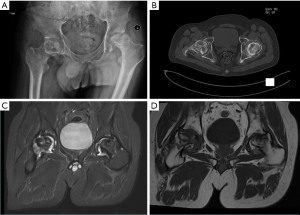

Although medication was administered, there was no significant relief in hip pain symptoms. The X-ray examination of the patient showed severe collapse of both femoral heads, narrowing of the hip joint space, and subluxation of the left femoral head in our hospital (Figure 2). Computed tomography (CT) examination showed that the patient’s bilateral femoral head joint surfaces were fractured, and multiple cystic changes and necrosis occurred within the femoral head (Figure 2). Hip joint magnetic resonance imaging (MRI) examination showed mixed signals in the femoral head, as well as typical “double line sign” and “map sign” manifestations (Figure 2). The patient was diagnosed with bilateral ANFH [Association Research Circulation Osseous classification stage IV (ARCO IV)] according to the diagnostic criteria of the ARCO (6).

The preoperative laboratory test results of the patient showed severe deficiencies in red blood cells, granulocytes, and platelets, elevated venous blood glucose, and no significant abnormalities in chest CT, lung function, and ultrasound examinations of abdominal, cardiac, and lower limbs vascular. We administered multiple component infusions of red blood cells and platelets before surgery. To increase the number of platelets, we orally took 75 mg of eltrombopag tablets daily. We subcutaneously injected recombinant human granulocyte colony-stimulating factor (300 µg) the following day to increase granulocyte levels. We maintained the intravenous glucose of this patient through continuous insulin administration and a strict diabetic diet. We maintained the patient’s blood levels, blood sugar, biochemistry, and coagulation function at a reasonable level during the perioperative period. We performed THA on the patient’s hip joint through the posterior lateral approach under general anesthesia in January 2024 and March 2024, and the two surgeries went successfully without any adverse events. We performed pelvic X-ray examination after surgery and found that the hip joint prosthesis was in good position (Figure 3). The patient had no obvious discomfort symptoms after getting out of bed and moving around. We followed up for 6 months and both hip functions recovered well (Harris Hip Score =90 points).